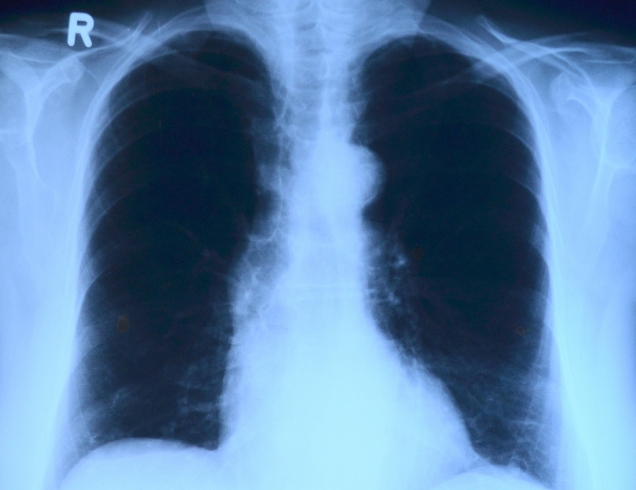

호흡기질환

호흡기 질환은 바이러스나 세균의 감염, 흡연,유전등 다양한원인으로 발생됩니다.

- 호흡기 질환은 다양한 원인으로 발생할 수 있습니다. 대표적으로는 바이러스나 미생물에 의한 감염으로 인한 호흡기 질환인 감기, 독감, 폐렴 등이 있습니다.또한 공기오염물질이나 환경오염, 흡연 등과 같은 외부 요인도 호흡기 질환을 유발하는 원인으로 작용할 수 있습니다. 이러한 외부 요인은 폐에 자극을 주어 호흡기 기관의 염증을 유발해 호흡기 질환을 유발할 수 있습니다.또한 유전적인 요인도 호흡기 질환을 일으키는 원인 중 하나입니다. 만약 가족에서 호흡기 질환을 앓고 있거나 호흡기 질환에 대한 취약한 유전자를 가진 경우 해당 질환의 발생 가능성이 높아집니다.마지막으로 건강한 생활습관과 올바른 식습관을 유지하지 않는 것도 호흡기 질환의 원인 중 하나입니다. 불규칙한 식습관, 부족한 수면, 야외 활동 부족, 과도한 음주나 스트레스 등은 호흡기 질환의 발생 위험을 높입니다.